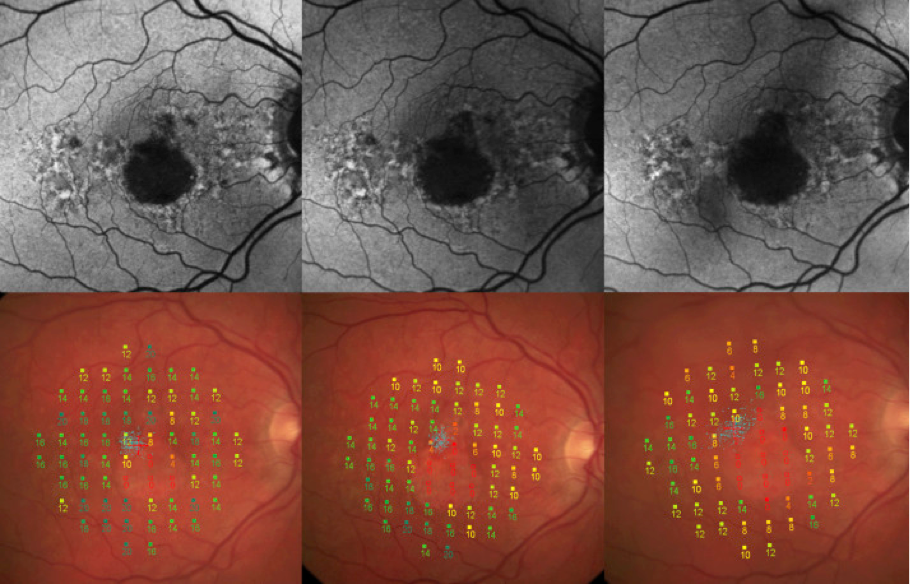

Microperimetría

La microperimetría evalúa la capacidad del ojo para percibir los estímulos luminosos en diferentes partes de la retina. Se trata de un dispositivo de imagen de la retina con una prueba de campo visual en la que se puede mapear espacialmente la función de los fotorreceptores. Los fotorreceptores son las células sensibles a la luz de la retina. En la microperimetría, la retina se expone a pequeños puntos de luz de distintas intensidades. El paciente, al pulsar un botón, confirma haber percibido el estímulo luminoso.15 A continuación, se identifican las posibles pérdidas de campo visual en la retina de la persona.15